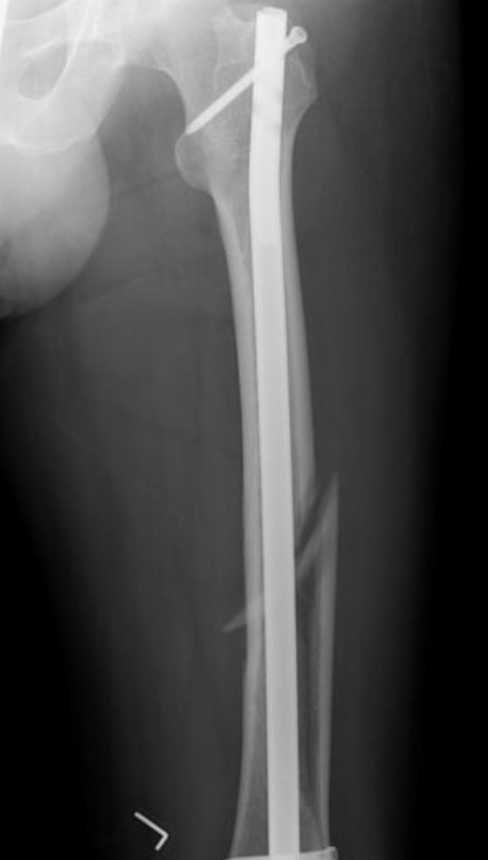

Dr. Carlin had to undergo surgery after an encounter with the hardy pearson hall staircase. After breaking which bone did he need nails and rods to be put in?

What is femur.

This singer with the last name "Stewart" recently had ankle fusion surgery. In this procedure surgeons commonly utilize three specific materials, two of which are plates and screws. What is the third material that is pictured and shares an epithet with the singer?

What is rod.